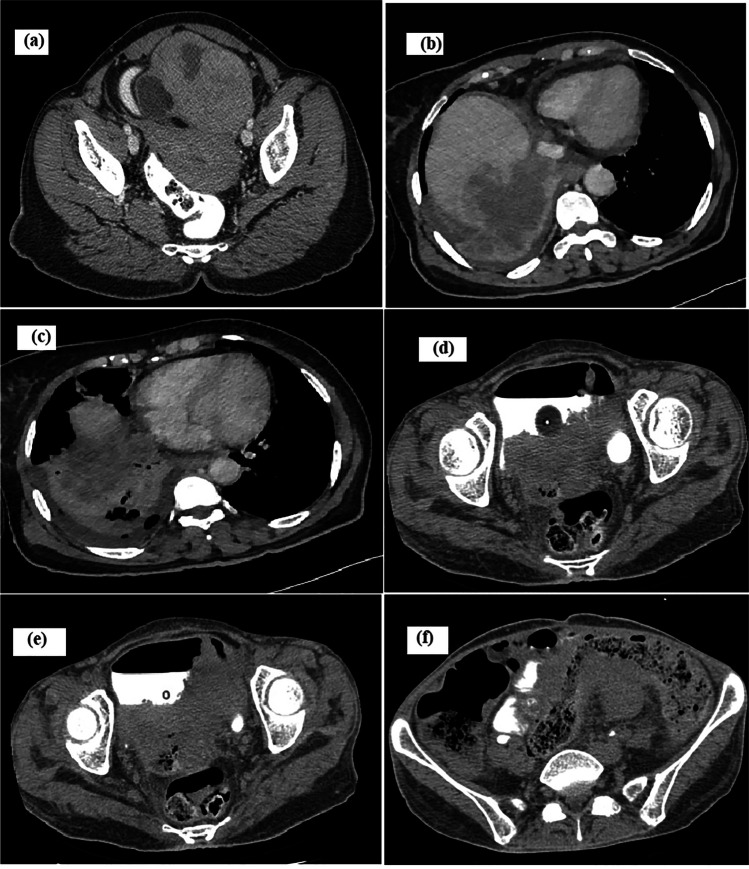

Fig. 1.

Radiology images. a Contrast-enhanced computed tomography (CECT) of the abdomen/pelvis showed heterogeneous enhancing left adnexal mass with solid areas, fluid/fat densities, and macrocalcifications. b CECT of the thorax/abdomen showing rupture of right liver lobe lesion into the right pleural cavity. c CECT of the thorax/abdomen showing necrotic bilobar liver lesions. d–f CT of the abdomen/pelvis showing a large irregular cavitating pelvic mass containing air pockets with vaginal infiltration (d), bladder infiltration (e), and rectosigmoid infiltration (f)

A 64-year-old lady, P3L3, presented with abdominal pain and early satiety of 5 months duration. She denied having bleeding per vaginum, dyspnea, weight loss, or other systemic symptoms. She reported no addictions/drug allergies and was on regular medications for hypothyroidism and hypertension. At presentation, she was of Eastern Cooperative Oncology Group Performance Status (ECOG PS) 1. A firm mass of size 20 × 15 cm was filling the infra-umbilical quadrants and a pouch of Douglas (POD) deposit was appreciated. Contrast-enhanced computed tomography (CECT) of the abdomen/pelvis showed heterogeneous enhancing 15.5 × 13.7 × 9.5 cm left adnexal mass with solid areas, irregular fluid/fat densities and macrocalcifications probably malignant teratoma, along with POD mass and multiple enlarged para-aortic nodes (Fig. 1a). Her CA-125 was 250 U/ml and CEA was 7.6 ng/ml. Fine needle aspiration cytology from POD suggested adenocarcinoma (Fig. 2a). The multidisciplinary tumour board decided for neoadjuvant chemotherapy with a provisional diagnosis of advanced carcinoma ovary. Post 6 cycles of taxane/carboplatin neoadjuvant chemotherapy, total abdominal hysterectomy (TAH), bilateral salpingo-oophorectomy (BSO), omentectomy, para-aortic lymph node debulking, resection of the involved ileum and bowel anastomosis was done. Grossly, the left adenexal mass measured 20 × 16 × 4 cm, which on microscopy showed moderately differentiated SCC and well-differentiated neuroendocrine tumour arising from a left OMCT (Fig. 2b–d). The SCC component infiltrated the peri-intestinal fat and muscularis propria. Lymphovascular emboli were seen. Three out of five para-aortic lymph nodes showed metastasis from neuroendocrine tumour, which were immunoreactive for synaptophysin and chromogranin (Fig. 2e–g). The MIB was 5–8%.

Within 2 months, she progressed with abdominal symptoms. CECT of the thorax/abdomen showed necrotic bilobar liver lesions with rupture of right lobe lesion into the right pleural cavity, multiple nodular lung lesions, periportal/pericardiophrenic nodes, and multiple deposits in gastrohepatic ligament/mesentery (Fig. 1b, c). Liver biopsy showed metastasis from SCC. The patient opted for best supportive care and succumbed to death after 1 month.

A 47-year-old postmenopausal lady, P3L3, with no comorbidities, presented to us with abdominal pain/distension of 6 months duration. Magnetic resonance imaging (MRI) of the abdomen revealed a left ovarian encapsulated, thin-walled lesion measuring 18 × 17 × 11 cm with enhancing irregular internal septae and loculations. Her ECOG PS was 2 and she underwent TAH BSO, appendicectomy, and infracolic omentectomy. The 15 × 15 × 10 cm left ovarian mass was patholocally suggestive of OMCT with MT into SCC with vascular invasion. The omentum was involved with a metastatic SCC deposit. She defaulted after receiving 2 cycles of ifosfamide/cisplatin and unfortunately, presented after 4 months in a moribund state with hypotension. On clinical examination, she had rectovaginal fistula. CT of the abdomen/pelvis showed a large irregular cavitating pelvic mass of size 12 × 12 × 9 cm, with air pockets inside. The mass was in continuity with vaginal lumen. It infiltrated rectosigmoid superiorly and bladder inferiorly with fistula formation and intravesical extension (Fig. 1d–f). The small bowel loops also had fistulous communication to the mass at multiple sites. The patient was managed conservatively and she expired after 2 weeks.